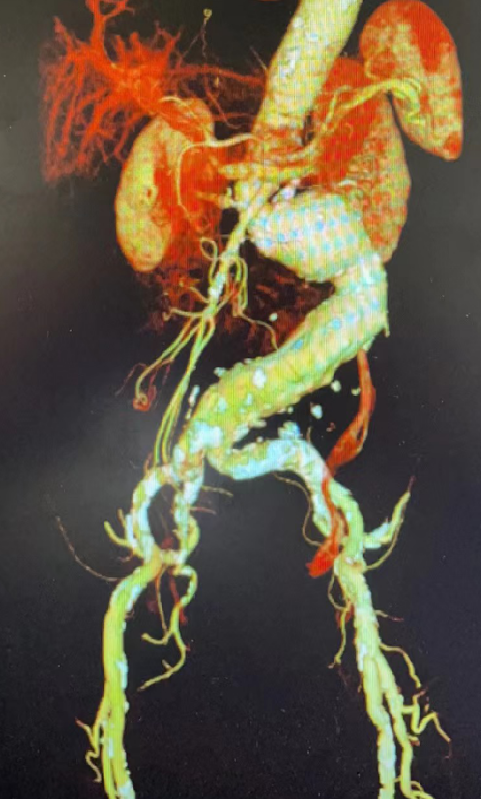

2. 检查降主动脉、腹主动脉及髂动脉入路的形态、钙化、狭窄及扭曲程度(影响支架输送及定位)

需要注意髂动脉钙化、狭窄情况,确保主体支架能顺利进入并调整位置。

髂动脉严重钙化、狭窄:主体支架能否进入?能否顺利调整位置?

复杂瘤颈(钙化、扭曲):增加束径至30-50%,便于术中主体支架的位置调整和窗孔对位

严重扭曲需延长鞘辅助,确保分支支架顺利进入目标血管